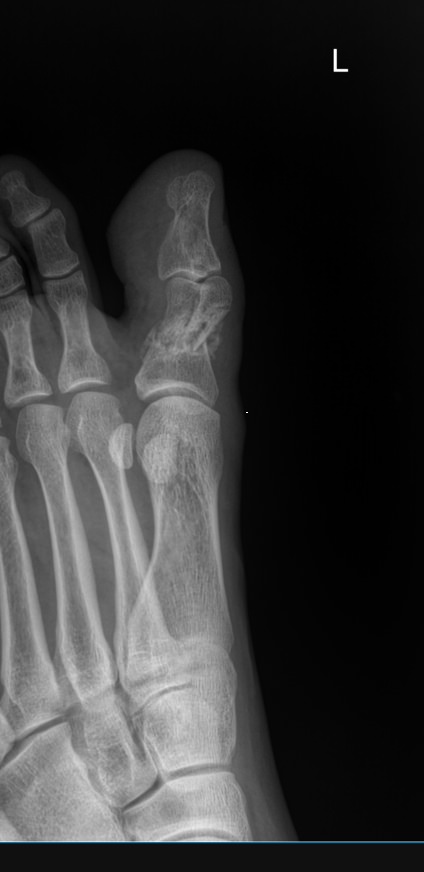

Все изменения хорошо видны на рентгеновском снимке, он и будет первым, а чаще и основным, видом диагностики. Основываясь на рентгенограмме, а также лабораторных показателях, врач выбирает оптимальное лечение и дальнейшее ведение болезни.

На прицельном снимке будут отчетливо видны следующие изменения:

• Суставная щель может быть расширена, в том числе неравномерно, или сужена, в ней обнаруживается выпот или участки обызвествления;

• Суставные поверхности могут не соответствовать друг другу из-за вывиха;

• В тканях кости и надкостницы обнаруживаются участки разрежения, уплотнения, разрастания, воспаления, перелома;

• Утолщение мягких тканей;

• Новообразования, при наличии.